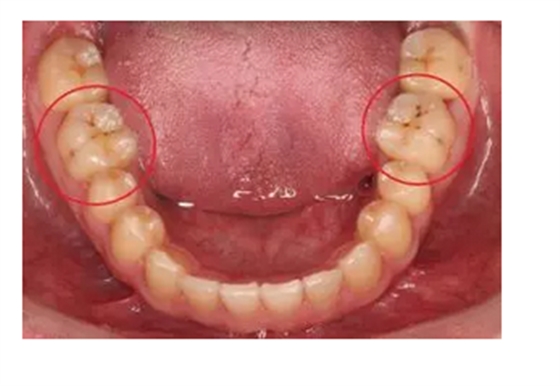

牙齒出現(xiàn)的齲壞,從外面看就表現(xiàn)為一個黑點,通常位于窩溝點隙(牙面上點狀或線狀凹陷)。齲齒的罪魁禍?zhǔn)资强谇恢械哪承┘?xì)菌,但它們破壞牙齒也是需要時間的,從初期的變色到最終形成齲洞,通常需要1年半到2年。在此期間,我們多留心自己的牙齒,完全可能把齲壞扼殺在萌芽階段。如何才能及時發(fā)現(xiàn)這種隱匿的蛀牙呢?找位好牙醫(yī),半年檢查牙齒!

一旦確認(rèn)牙齒上的小黑點是齲齒就應(yīng)該盡早修補(bǔ),以阻止病變的發(fā)展。如果任由其繼續(xù)發(fā)展就會變成明顯的齲洞,這時患者會對冷熱酸甜等食物刺激敏感;當(dāng)損傷進(jìn)一步到達(dá)牙髓(即老百姓說的“牙神經(jīng)”),就會疼痛難忍,嚴(yán)重影響日常生活。